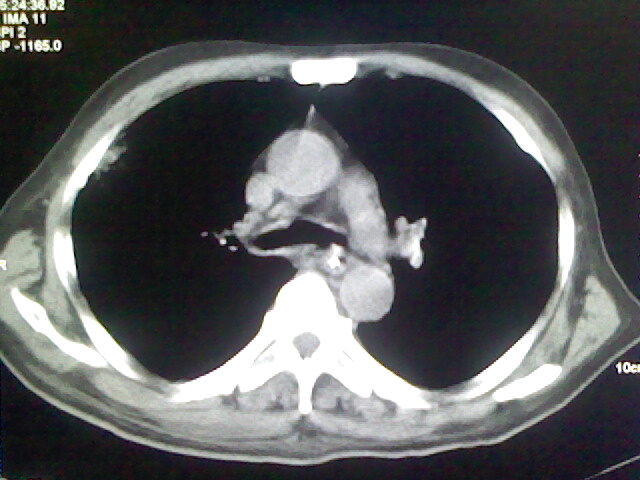

男,70岁,脑出血,长期卧床,左侧背部可触及肿块

右肺病灶考虑炎症性。

右肺病灶考虑炎症性

考虑右肺及左肺下叶炎症。

右侧肺部见片状密度增高影,边缘模糊。考虑炎症。另食管壁增厚。

右肺上叶前段病呈楔形,其尖端指向肺门,考虑肺动脉栓塞可能性大.